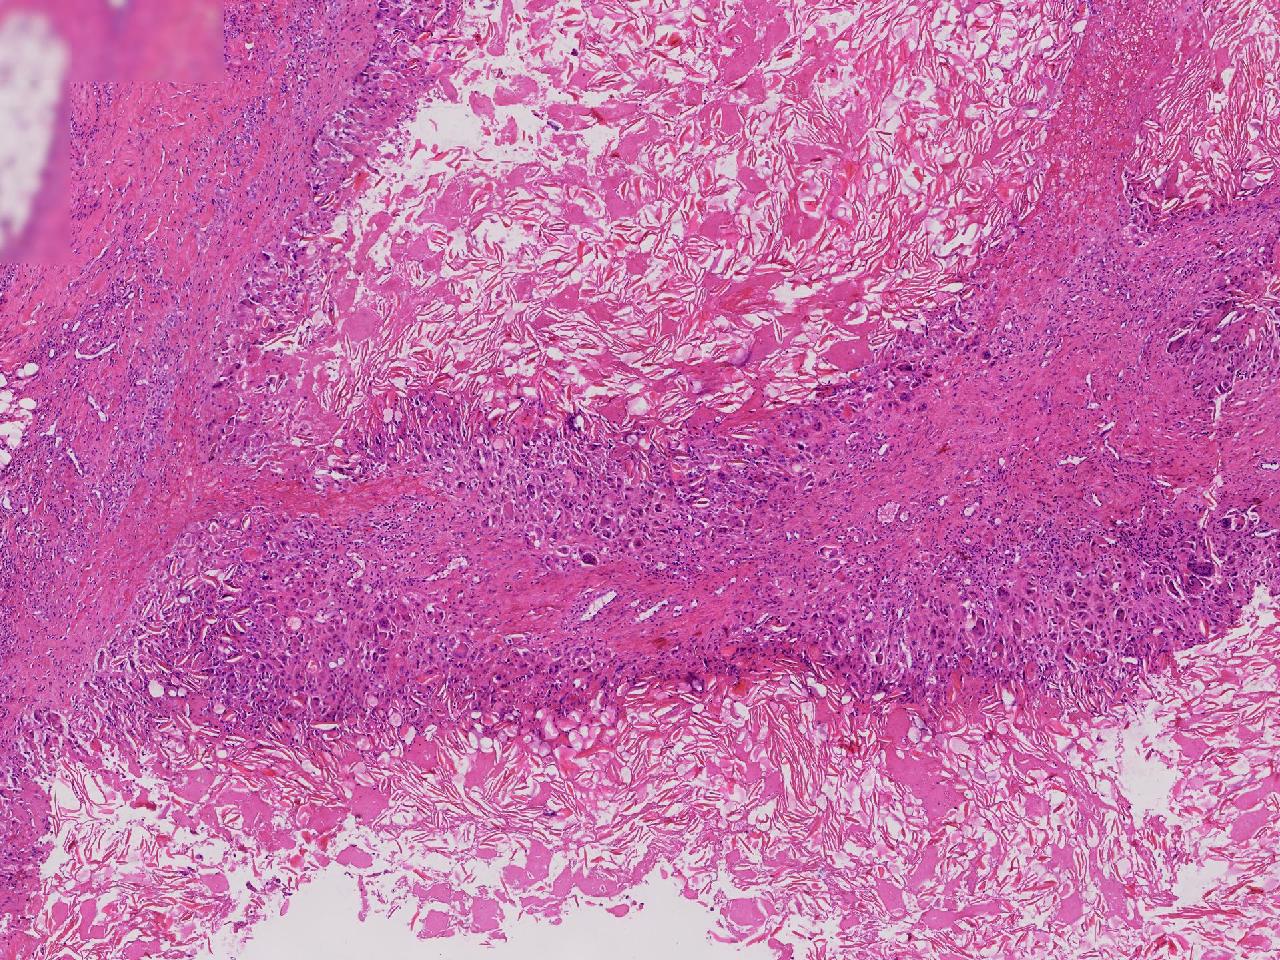

皮样/表皮样囊肿伴周边异物巨细胞反应?

右侧臀部皮下肿物10余年,渐增大,无破溃,无疼痛。

右侧臀部皮下肿物

囊性肿物一个,直径2.5厘米,肿物位于皮下。

异物肉芽肿性炎?

表皮样囊肿伴异物肉芽肿性炎。